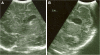

Prenatal ultrasonographic detection of unilateral cerebral ventriculomegaly arises suspicion of pathological condition related to cerebrospinal fluid flow obstruction or cerebral parenchimal pathology. Dyke-Davidoff-Masson syndrome is a rare condition characterized by cerebral hemiatrophy, calvarial thickening, skull and facial asymmetry, contralateral hemiparesis, cognitive impairment and seizures. Congenital and acquired types are recognized and have been described, mainly in late childhood, adolescence and adult ages. We describe a female infant with prenatal diagnosis of unilateral left ventriculomegaly in which early brain MRI and contrast enhanced-MRI angiography, showed cerebral left hemiatrophy associated with reduced caliber of the left middle cerebral artery revealing the characteristic findings of the Dyke-Davidoff-Masson syndrome. Prenatal imaging, cerebral vascular anomaly responsible for the cerebral hemiatrophy and the early clinical evolution have never been described before in such a young child and complete the acquired clinical descriptions in older children. Differential diagnosis, genetic investigations, neurophysiologic assessments, short term clinical and developmental follow up are described. Dyke-Davidoff-Masson syndrome must be ruled out in differential diagnosis of fetal unilateral ventriculomegaly. Early clinical assessment, differential diagnosis and cerebral imaging including cerebral MRI angiography allow the clinicians to diagnose also in early infancy this rare condition.